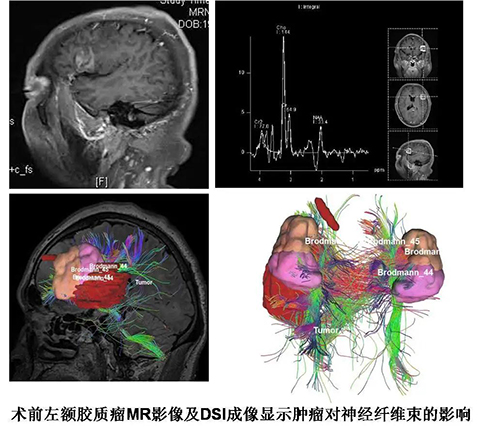

患者是一名47岁的企业管理人员,因阵发性言语障碍伴口角抽搐来院就诊,被确诊为胶质瘤。经颅脑MR检查,医师发现肿瘤位于左侧半球语言功能区。如果按照传统方法切除肿瘤,术中极有可能误伤到上述功能性组织,即使成功切除肿瘤,患者术后也可能出现严重的语言障碍而导致失语。神经外科王国栋副主任主持讨论为患者制定了严密的个体化手术方案——术中唤醒技术及术中神经电生理功能区定位监测技术。脑功能区胶质瘤手术技术是目前国内外神经外科手术领域探讨的热点与难点问题,术中唤醒下皮质及皮质下直接电刺激技术是目前大脑功能区定位的“金标准”。在切除肿瘤前将患者 “术中唤醒”,利用神经电生理技术精确定位语言功能区,从而实现在监测和保护患者重要功能的情况下最大程度的切除病灶,有效避免术后永久性神经功能损伤的发生,能显著提高患者术后生存质量。术前在神经外科主任庞琦的大力支持下,在王国栋副主任的详细指导下,神经外科手术团队反复对手术体位、语言中枢精准定位、癫痫预防等困难反复斟酌并制定预案。

5月9日,手术开始,麻醉科主任张孟元、王旭主治医师对唤醒麻醉进行精准控制,疼痛科孙涛主任、杨聪娴主治医师对头皮神经干精准阻滞,神经外科电生理秦艳宇护士进行术中监测,山东省影研所超声介入诊疗科丛林主治医师精准定位,山东省影研所高飞副主任医师DSI纤维成像,神经外科东病区和手术室护士们密切配合。将患者唤醒后,郑志明副主任医师手术团队开始对患者进行直接脑皮层电刺激,在患者意识完全清醒的状态下对视觉语言、听觉语言、语言连贯性、语义错误、命名进行功能测试。“从1数到10,再从10数到1”、“这张图片是什么”、“请动动你的脚趾,闭眼睛同时伸舌头”等测试在术中逐一展开,在与患者的聊天过程中准确地标记出语言功能区,规划出躲避这些功能区的“手术路径”。1小时后,肿瘤被成功切除。手术结束后,当患者正常开口说话时,参与手术的每一个人都长出一口气。患者清醒着被送回了病房,无任何不良记忆,术后患者的语言、运动等神经功能均完成正常。